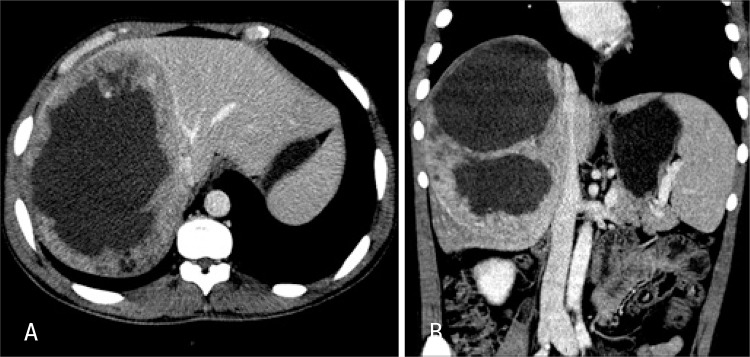

The laboratory test results showed normal complete blood count and liver function tests, negative serology for hepatites, slight increase in canalicular enzymes and tumor markers within normalcy. Abdominal ultrasound showed a heterogeneous mass in the right hepatic lobe measuring 12x10cm, with a solid-cystic content. Computed tomography demonstrated enlarged liver due to the right hepatic lobe that presented an extensive infiltrating lesion with poorly-defined contours, a liquefied center and the periphery was partially enhanced by contrast medium. There was no further involvement of other organs (Figure 1A and B).

Figure 1. (A) Axial computed tomography image - portal phase - middle hepatic vein - contact with lesion. (B) Coronal computed tomography image.